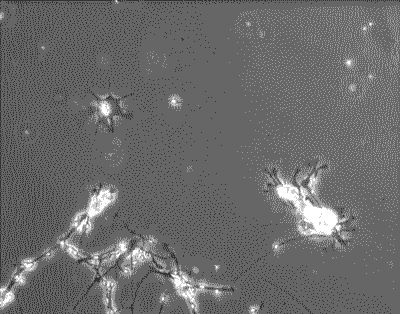

培养皿中的脑神经元正在试图相互连接